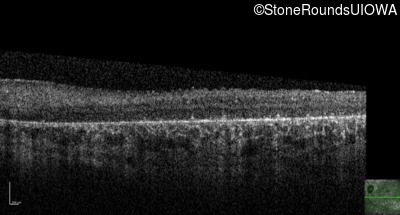

Visit at age: 28 years

Optical Coherence Tomography - Left - Hand Motion

Exemplar / OCT Stack

OCT Stack